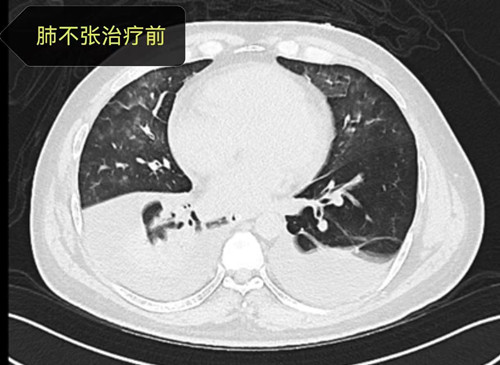

一周后,曾先生生命体征逐渐趋于平稳,神志也逐渐清醒,但吸氧浓度仍较高,超过60%氧浓度,复查肺部CT显示双下肺仍有大片不张。进入下一阶段的撤机拔管环节,呼吸治疗师曾娟利每为其评估肺和膈肌功能,实施肺复张及肺康复,逐步降低各项呼吸机支持参数。经过呼吸三科团队的有效综合治疗,曾先生吸氧浓度有下降,床旁肺部超声提示肺不张明显有改善,几天后曾先生成功脱离有创呼吸机、拔除气管导管,延续无创呼吸机治疗,出院前复查胸部CT,显示肺已完全膨胀开,肺部感染已基本控制。曾先生一路闯过了呼吸衰竭、重症感染、休克、困难脱机、机体康复等重重难关,恢复自理能力,顺利康复出院。出院前杨欢副主医生为其进行健康宣教、戒烟、规范用药和无创呼吸机治疗。